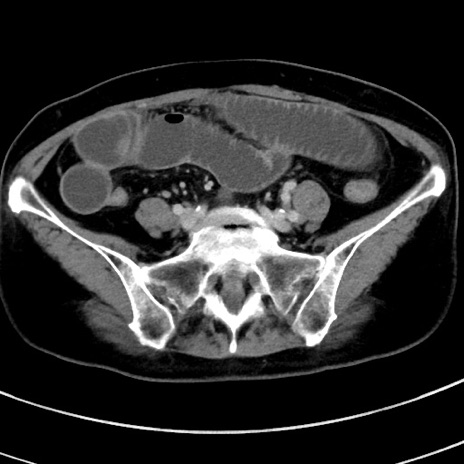

症例9(横断像)

【症例】 60歳代女性

【主訴】むかつき、みぞおちの痛み

【現病歴】3日前よりむかつきがあり、食事がとれない。

【既往歴】糖尿病

【身体所見】発熱なし、心窩部圧痛軽度あるも、腹膜刺激症状なし。

【データ】WBC 7400、CRP 1.92